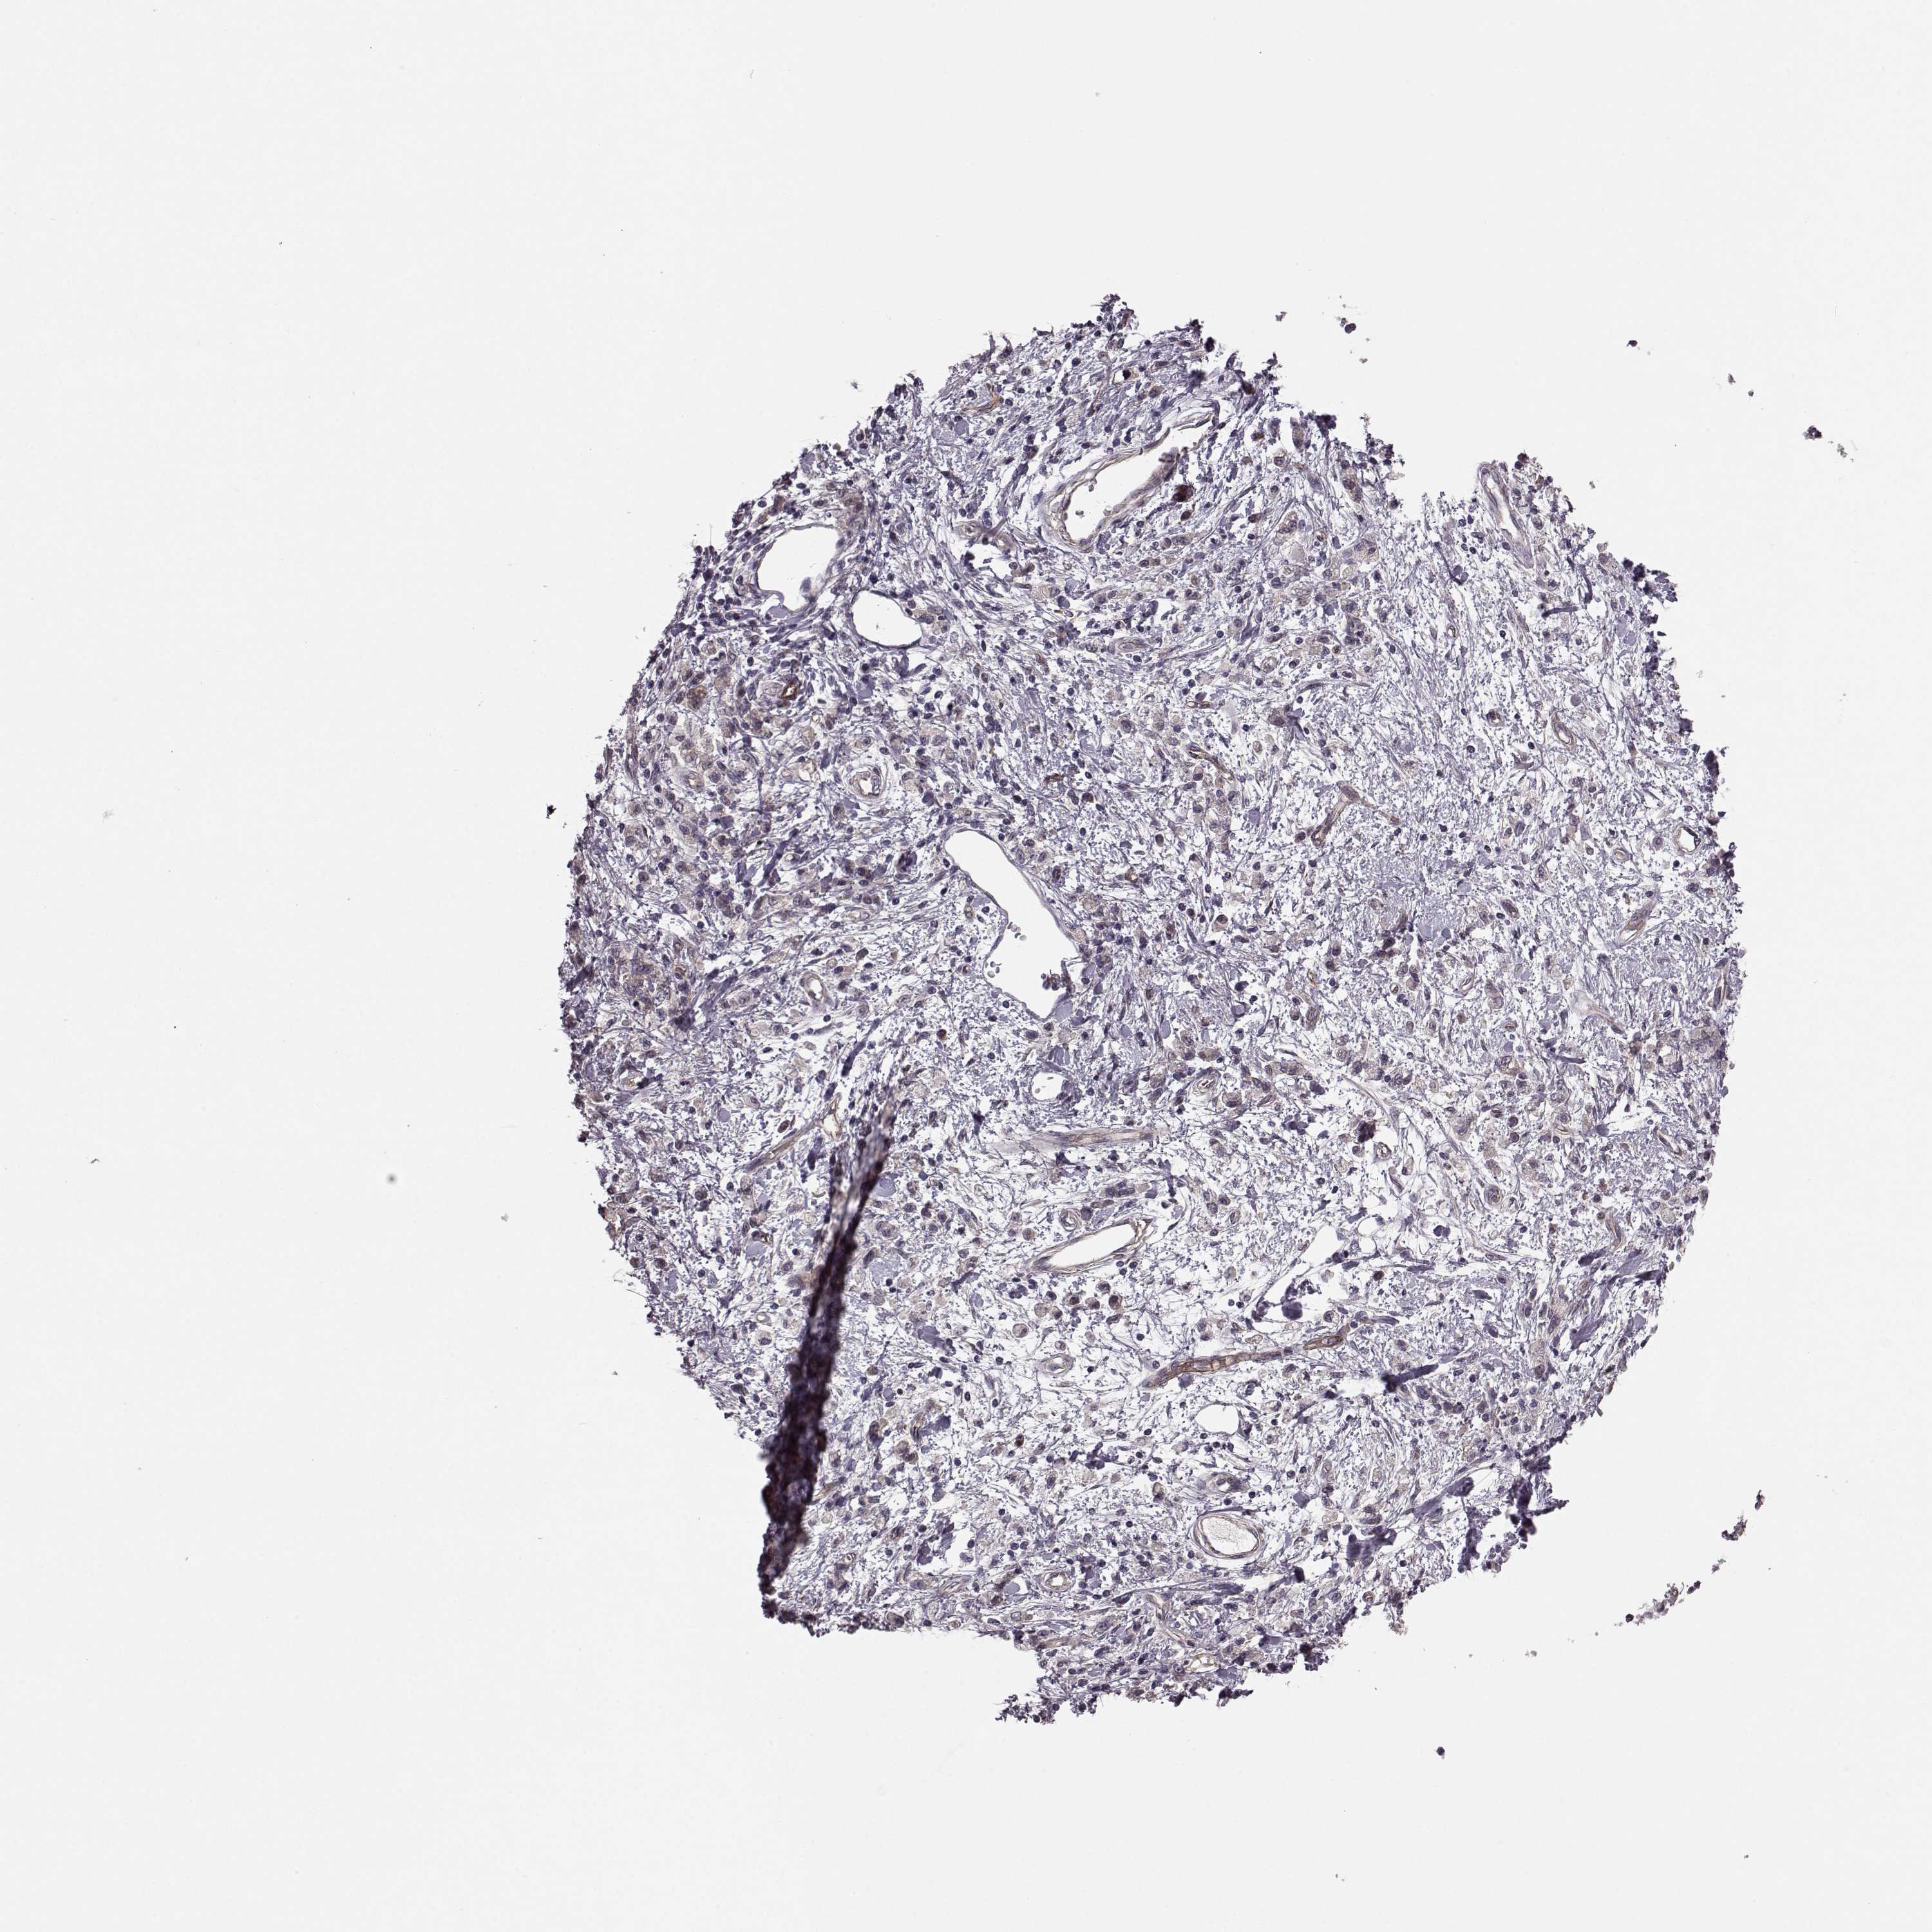

STOMACH CANCER - Protein expressioni

A mouse-over function shows sample information and annotation data. Click on an image to view it in a full screen mode. Samples can be filtered based on level of antibody staining by selecting one or several of the following categories: high, medium, low and not detected. The assay and annotation is described here.

Note that samples used for immunohistochemistry by the Human Protein Atlas do not correspond to samples in the TCGA dataset.

Antibody stainingi

Antibody staining in the annotated cell types in the current human tissue is reported as not detected, low, medium, or high, based on conventional immunohistochemistry profiling in selected tissues. This score is based on the combination of the staining intensity and fraction of stained cells.

Each image is clickable and will lead to virtual microscopy that enables deeper exploration of all samples and also displays staining intensity scores, fraction scores and subcellular localization as well as patient and tissue information for each sample.

Antibody HPA034631

Antibody HPA071347

Antibody CAB033265

Antibody CAB037325

Staining

High

Medium

Low

Not detected

Intensity

Strong

Moderate

Weak

Negative

Quantity

>75%

75%-25%

<25%

None

Location

Nuclear

Cytoplasmic/membranous

Cytoplasmic/membranous,nuclear

Adenocarcinoma, NOS

Adenocarcinoma, High grade